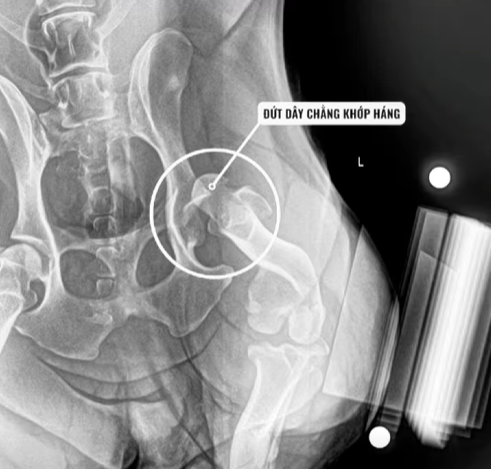

Qua quá trình thăm khám lâm sàng và chụp X-quang, các bác sĩ tại Bằng Phạm đã chẩn đoán chính xác: Bum bị đứt dây chằng khớp háng hoàn toàn.

chó bị đứt dây chằng khớp háng

Về mặt giải phẫu, dây chằng khớp háng đóng vai trò như một “dây neo” vô cùng quan trọng, giúp giữ chặt chỏm xương đùi nằm yên vị trong ổ cối xương chậu. khi chó bị đứt dây chằng khớp háng, toàn bộ cấu trúc khớp háng sẽ trở nên lỏng lẻo, dẫn đến tình trạng trật khớp, tê liệt vận động và gây ra những cơn đau dữ dội. Đứng trước chấn thương nghiêm trọng này, việc can thiệp ngoại khoa là con đường duy nhất để giải cứu Bum.